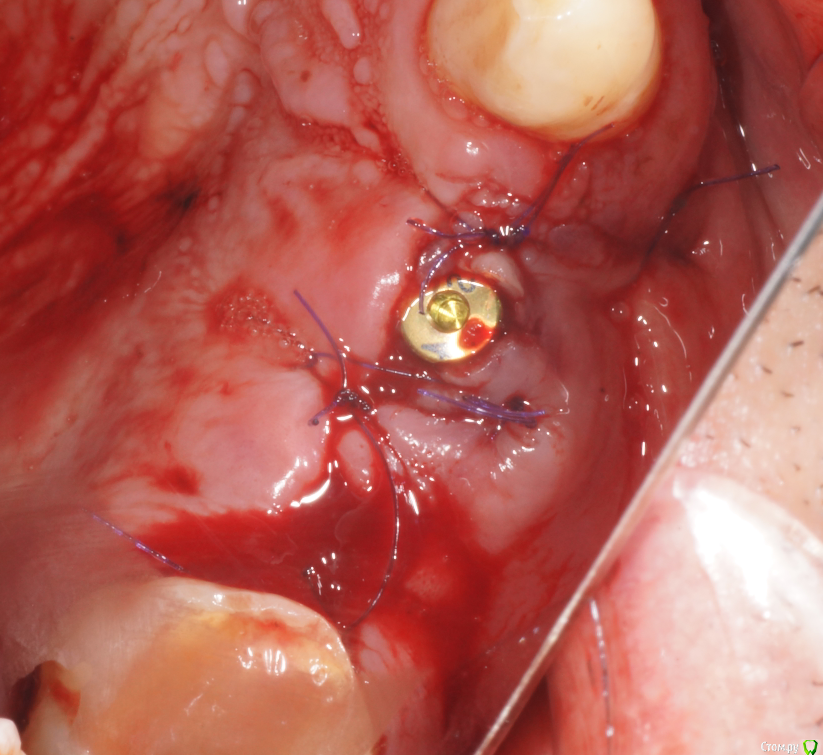

В начале планировал три имплантата, между зубами - 18,5 мм, в притык. Когда делал анестезию посмотрел наконец-то в рот (не смейтесь, внимательно посмотрел) - подумал, что моляр и два премоляра ортопед может не всунуть. Короче, передумал и решил ставить два и если че - пусть мостик или консоль делает.

Ах да, забыл совсем. Удалил по ходу действия 1.8, обратите внимание на пазуху по КТ - септа в проекции 1.7 так удачно отделила отекшую слизистую от области синуса)